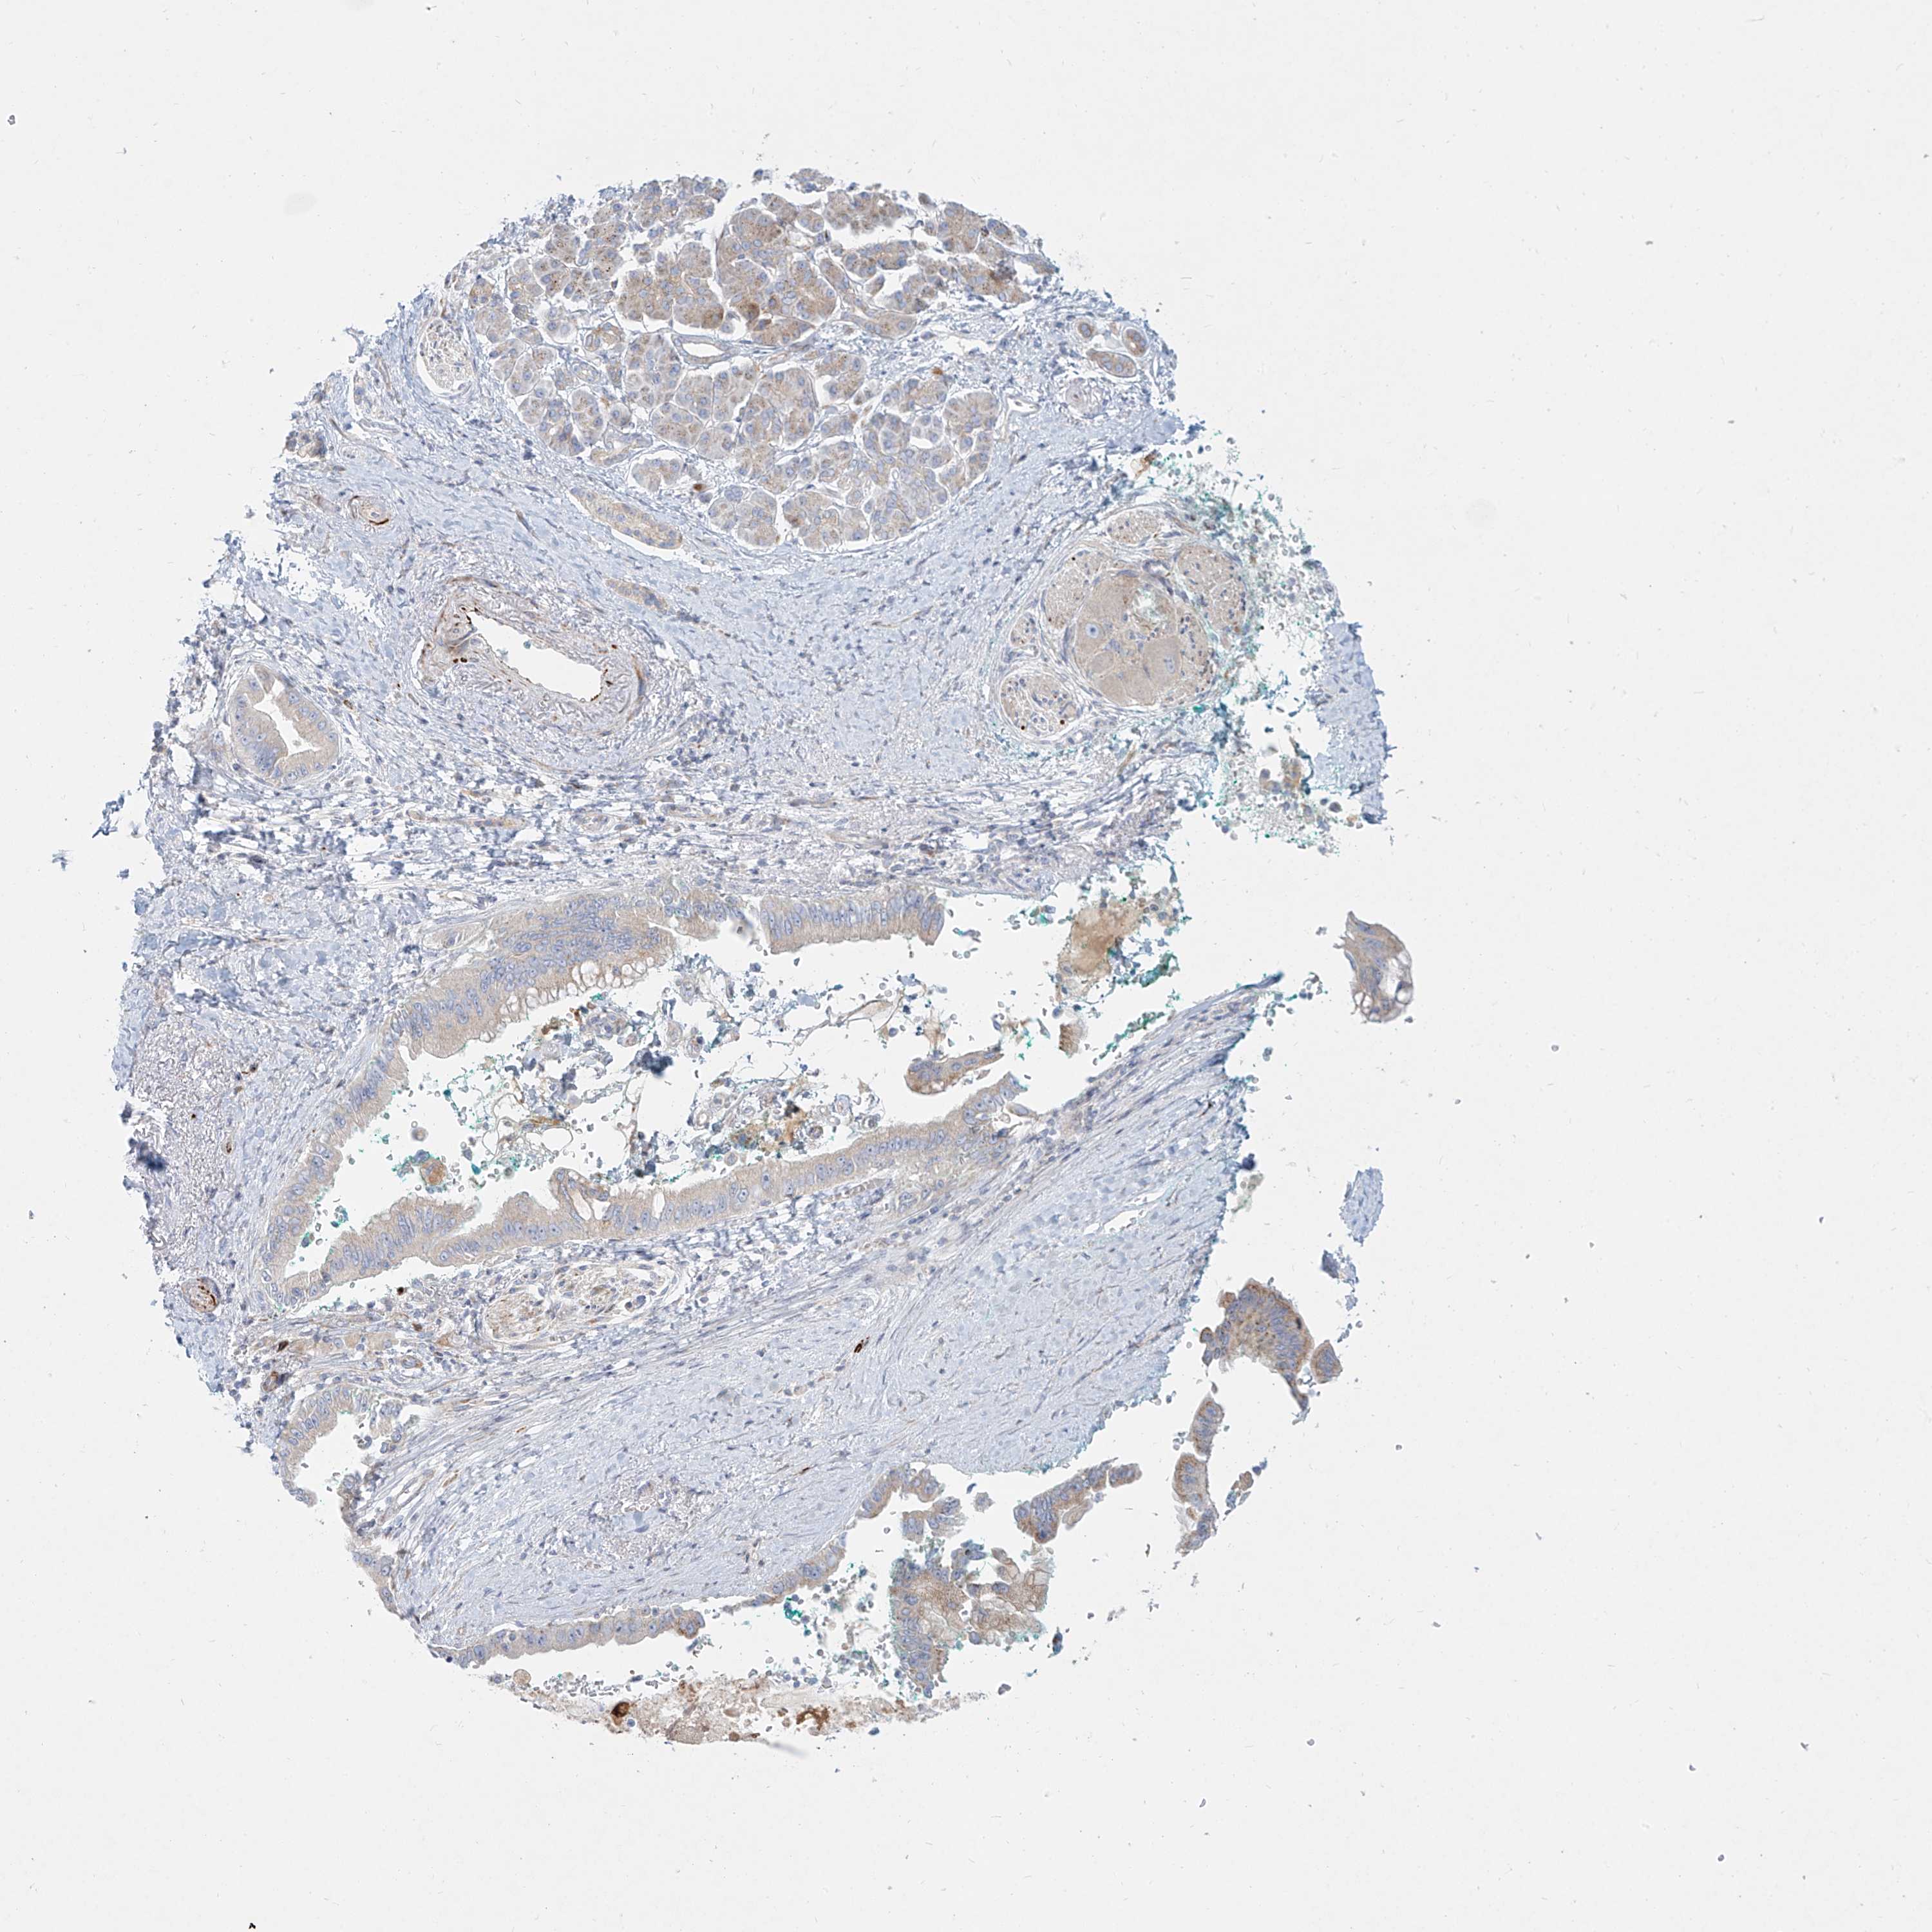

PANCREATIC CANCER - Protein expressioni

A mouse-over function shows sample information and annotation data. Click on an image to view it in a full screen mode. Samples can be filtered based on level of antibody staining by selecting one or several of the following categories: high, medium, low and not detected. The assay and annotation is described here.

Note that samples used for immunohistochemistry by the Human Protein Atlas do not correspond to samples in the TCGA dataset.

Antibody stainingi

Antibody staining in the annotated cell types in the current human tissue is reported as not detected, low, medium, or high, based on conventional immunohistochemistry profiling in selected tissues. This score is based on the combination of the staining intensity and fraction of stained cells.

Each image is clickable and will lead to virtual microscopy that enables deeper exploration of all samples and also displays staining intensity scores, fraction scores and subcellular localization as well as patient and tissue information for each sample.

Antibody HPA031550

Antibody HPA031551

Antibody HPA031552

Staining

High

Medium

Low

Not detected

Intensity

Strong

Moderate

Weak

Negative

Quantity

>75%

75%-25%

<25%

None

Location

Nuclear

Cytoplasmic/membranous

Cytoplasmic/membranous,nuclear

Adenocarcinoma, NOS